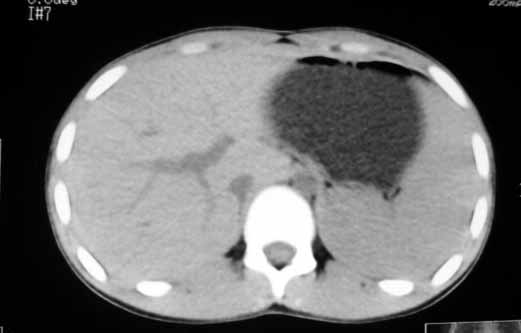

以下是引用zhangzhongshou在2007-5-22 21:04:00的发言:[br]1、脾肿大[br]2、脾脏低密度影,血管瘤?脾梗塞不能除外,建议增强扫描。

以下是引用dyqct在2007-5-22 20:45:00的发言:[br]巨脾,可疑梗塞,建议增强、查血象进一步检查

以下是引用liuyue在2007-5-23 7:57:00的发言:[br]腹主动脉周多个肿大淋巴结,脾大伴三角形低密度影,肠腔积气,考虑:1淋巴瘤2脾大伴梗塞3肠腔积气(肿大淋巴结压迫所致)